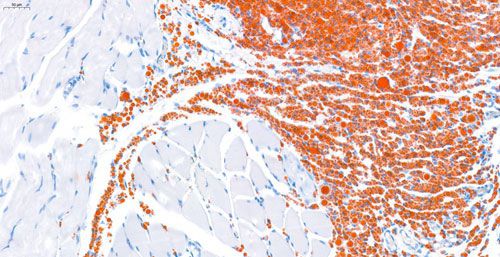

数字切片扫描是将物质化的玻片标本快速数字化的过程,能高效、高清晰、全信息的图像采集,是真正脱离显微镜的阅片方式。能长期保存,可满足临床、科研、教学等多种用途。油红O扫描是改善实验中无法完全避免的贴片不平整、叠片、厚等导致无法清楚成像问题。

实验结果展示: